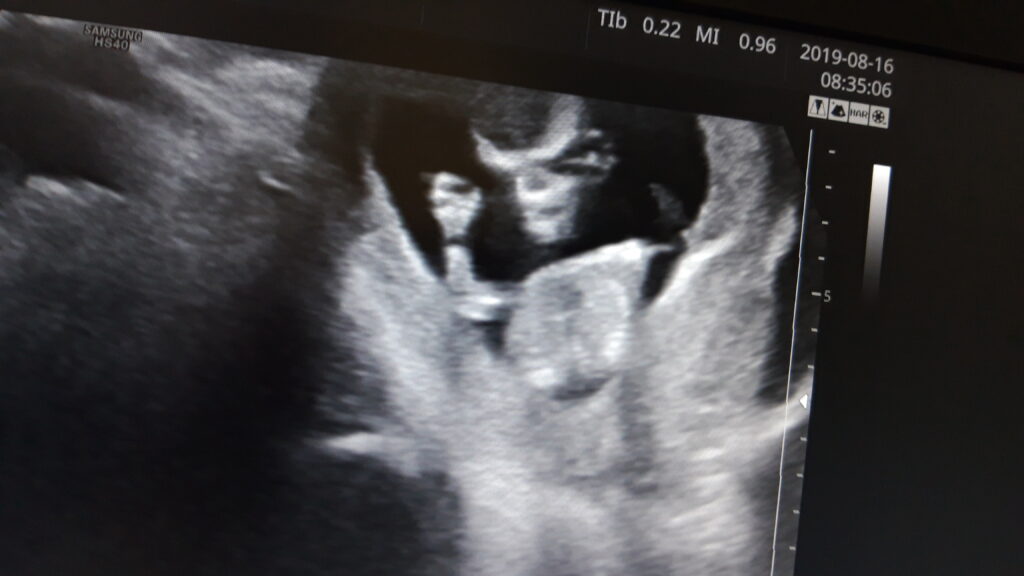

11. heti ultrahang

2019.08.16.2020.02.08. by sanyi

Mi kicsi alien-ünk.